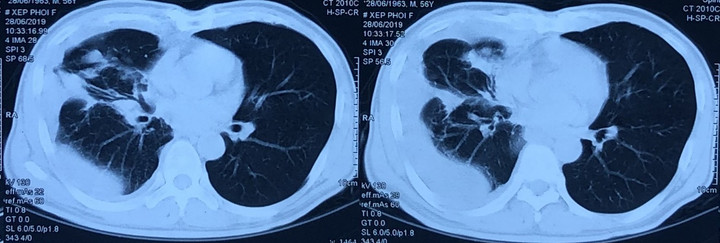

Đi khám tại Bệnh viện Xây dựng (Hà Nội), bà T. được chụp cắt lớp vi tính ngực hình ảnh u phổi phải, tràn dịch màng phổi phải, chuyển Bệnh viện Bạch Mai.

Hình ảnh chụp cắt lớp vi tính lồng ngực.